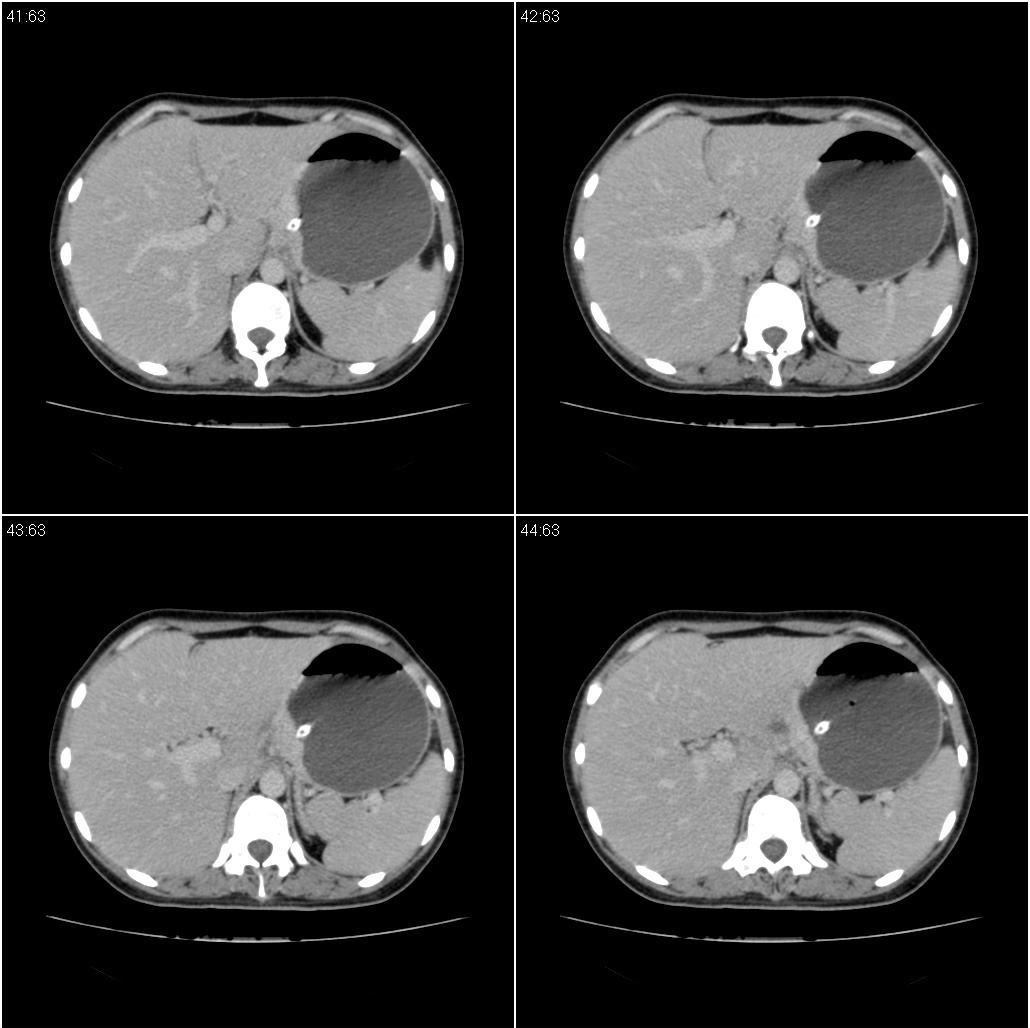

标题: CT21386:女性,33岁。4个月前因妊娠发现盆腔肿物。 [打印本页]

标题: CT21386:女性,33岁。4个月前因妊娠发现盆腔肿物。

女性,33岁。4个月前因妊娠发现盆腔肿物。ca-125: 1100

胃癌,幽门梗阻

胃癌,幽门梗阻.

胃幽门部癌伴小弯侧和腹腔淋巴结转移,胃内有胃管。

支持;胃癌【浸润】幽门梗阻.

胃窦贲门胃小弯好像都厚啊 ,胃窦处比较明显,而且胃腔扩张明显,考虑胃癌伴梗阻。

考虑胃癌伴腹腔内淋巴结转移。

支持;胃癌【浸润】幽门梗阻.胰头、胆囊及肝左叶受侵,副脾.